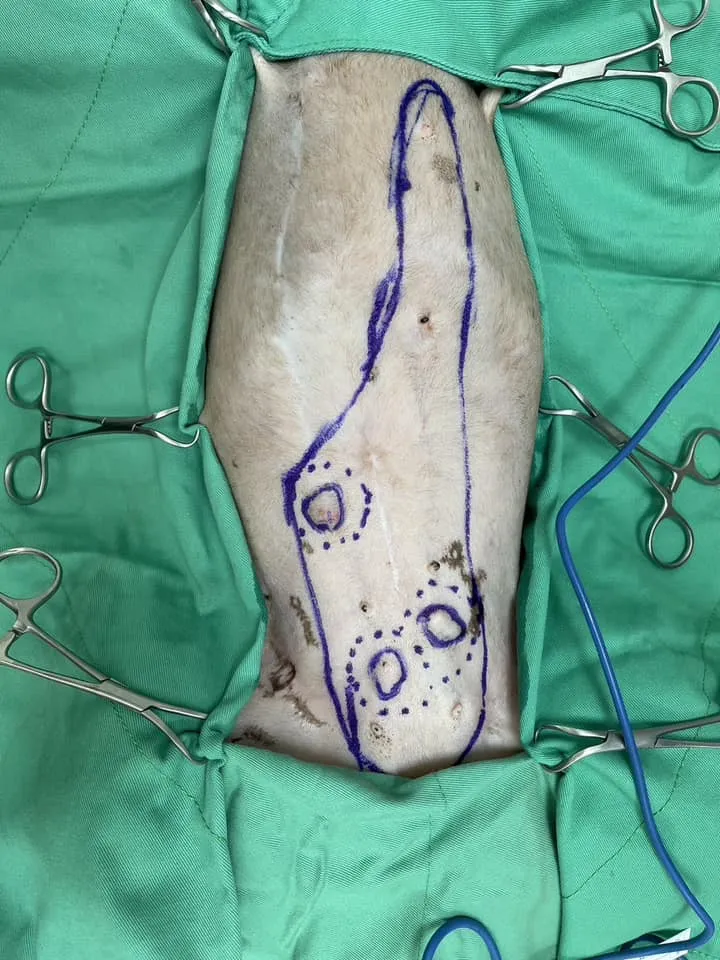

3.可能是需要用最大範圍去切除的小型腫瘤 :因為其多發的特性還有高的淋巴轉移機率,標準做法是整排乳腺切除或者至少要切除共用淋巴收集區的其他乳腺!

:因為其多發的特性還有高的淋巴轉移機率,標準做法是整排乳腺切除或者至少要切除共用淋巴收集區的其他乳腺!

今天這個病例,是曾經在兩年前切除過右側1-3區域乳腺的狗狗,當年也同時進行了子宮卵巢摘除術(OHE), 但過了兩年,既使當時其他乳腺無腫瘤的情況下,進行絕育手術,還是長出了多顆新的乳腺腫瘤! 這次一次將所有腫瘤與剩餘乳腺切除,並且在病理切片發現了兩顆惡性腫瘤 !不過幸好腫瘤都還小,使用這個術式完整切除後,復發率很低,切片結果也顯示不需術後化療,只要定期追蹤胸腔X光片即可!

!不過幸好腫瘤都還小,使用這個術式完整切除後,復發率很低,切片結果也顯示不需術後化療,只要定期追蹤胸腔X光片即可!

但看到長長的傷口,醫師覺得好心疼,術後一定要給予足夠的止痛才行! 我們採用buprenorphine 嗎啡類藥物,不容易造成嘔吐的副作用,更不會有非類固醇消炎藥消化道的副作用,真的很適合給予術後較虛弱的年老毛孩!

3.可能是需要用最大範圍去切除的小型腫瘤

今天這個病例,是曾經在兩年前切除過右側1-3區域乳腺的狗狗,當年也同時進行了子宮卵巢摘除術(OHE), 但過了兩年,既使當時其他乳腺無腫瘤的情況下,進行絕育手術,還是長出了多顆新的乳腺腫瘤! 這次一次將所有腫瘤與剩餘乳腺切除,並且在病理切片發現了兩顆惡性腫瘤

但看到長長的傷口,醫師覺得好心疼,術後一定要給予足夠的止痛才行! 我們採用buprenorphine 嗎啡類藥物,不容易造成嘔吐的副作用,更不會有非類固醇消炎藥消化道的副作用,真的很適合給予術後較虛弱的年老毛孩!